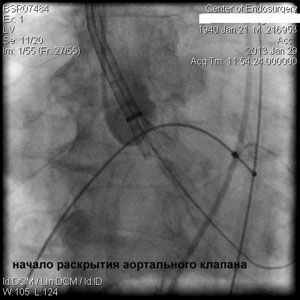

Через прокол (или маленький разрез) в артерии, в сжатом состоянии проводят искусственный клапан, который расширяется при его установке на месте поврежденного аортального клапана. После раскрытия клапан начинает функционировать и восстанавливает полноценную и нормальную работу аорты.